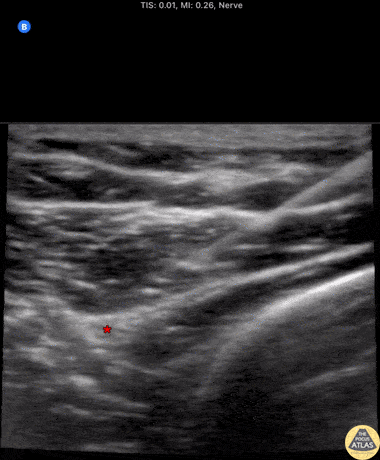

50s M with PMH IVDU presented with a dorsal hand abscess. To facilitate I&D, a radial nerve block was performed at the level of the elbow using the linear transducer and an in-plane approach. Injection of anesthetic seen adjacent to the radial nerve (*). The hyperechoic distal humeral cortex can be seen at the right of the image. Shortly after the block, I&D was able to be performed at bedside. Dr. Michael Heffler, PGY3 Denver Health Residency in Emergency Medicine